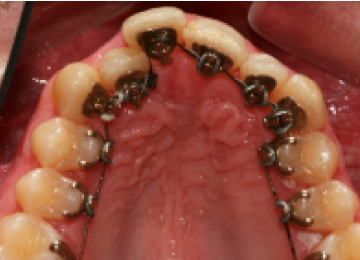

Одним из эффективных методов исправления прикуса у подростков после прорезывания зубов являются брекет-системы. Одним из препятствий к лечению во многих случаях становятся переживания подростков по поводу своего внешнего вида. В стоматологии "Интердентос" мы используем различные виды брекет-систем, в том числе и лингвальные, которые крепятся с внутренней стороны зубов.

Установка брекетов подросткам: фото До и После

- На 2-ом этапе происходит выбор наиболее эффективной и устраивающий подростка брекет-системы и установка.